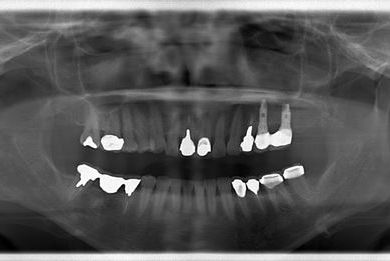

骨再生インプラント治療+セラミック治療+歯肉歯槽骨整形手術

| 治療方針 | ソケットリフトにより上顎洞を拳上し、骨再生法を行い、インプラント治療を可能にする。 | ||||||||||||||||||||||||||||||||

| 治療内容 | インプラント2本(ソケットリフト、GBR)、メタルボンドセラミッククラウン3本、歯肉歯槽骨整形手術 | ||||||||||||||||||||||||||||||||